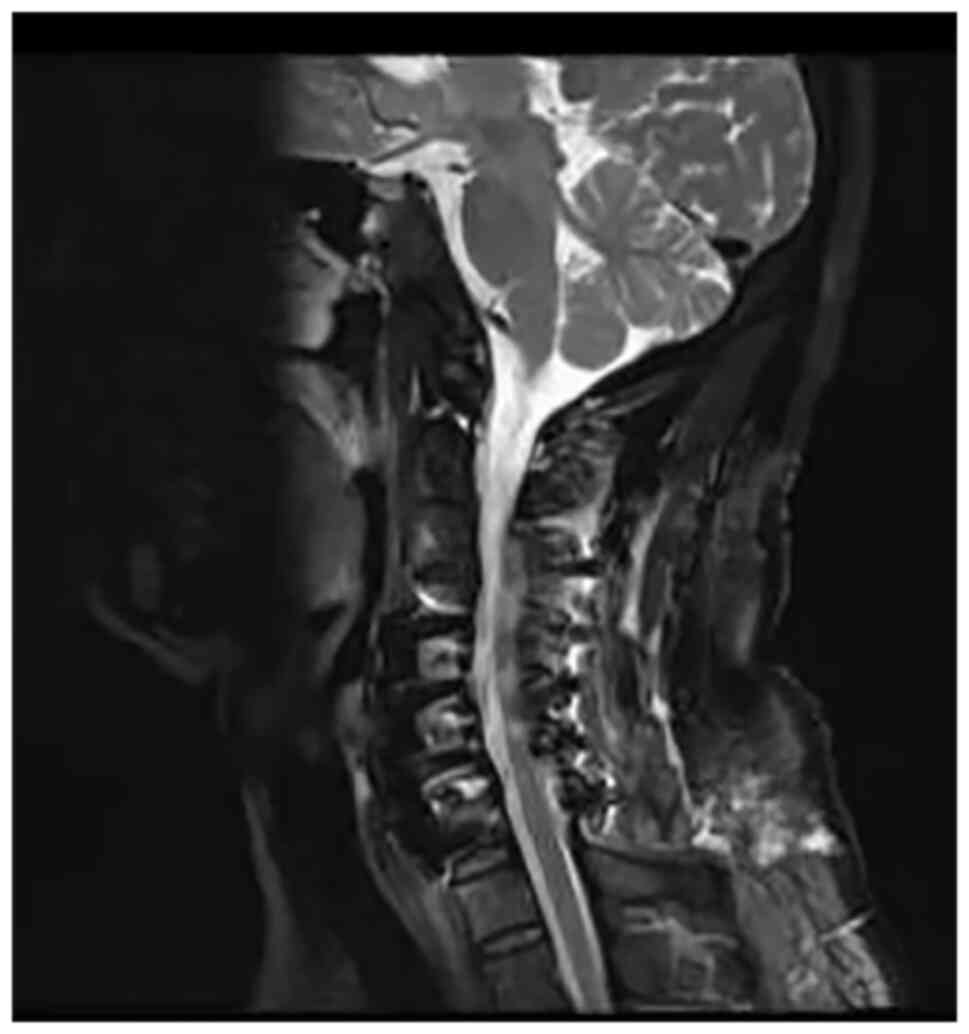

A 54-year-old man was admitted to Jinhua Municipal Central Hospital (Jinhua, China) in March 2021 with complaints of numbness and weakness in limbs and swelling in the neck. His myelopathic neurological examinations were negative. Physical examination determined that the strength in his limbs was normal. The preoperative cervical MRI scan showed degeneration and herniation of the C4-C7 discs (Fig. 1). He was diagnosed with CSM. Following routine preoperative preparation, ACCF C4-C7 surgery was performed. The cord was decompressed by removing the C4-7 disc material. The interbody cages were inserted into the C4-7 disc space and the plate was fixed on the C4-7 body anterior surface. X-ray imaging displayed satisfactory positioning of the pedicle screws. Following surgery, the patient's motor and sensory impairments gradually improved. However, on the 7th postoperative day, the patient was unable to move his legs and arms. Physical examination revealed upper limb strength of 3/5 and leg strength of 3/5 according to the Medical Research Council scale (7). Emergency MRI demonstrated T2 high intramedullary signal at C5-C6 level (Fig. 2). He was diagnosed with WCS and high dose methylprednisolone (80 mg, intravenously twice/day) combined with mannitol (250 ml, intravenously twice/day) and neurotrophic drug mecobalamin (0.5 mg, orally three times/day) were administered. However, symptoms did not improve and posterior cervical decompression surgery was performed 11 days after the initial ACCF operation. The second postoperative cervical MRI scan suggested that T2 high signal intensity had faded (Fig. 3). The patient recovered well postoperatively. On day 5 post-surgery, the patient was treated with hyperbaric oxygen therapy to decrease spinal cord edema and improve reperfusion injury (8). On the 10th day after the second surgery, the patient's muscle strength in the limbs recovered to grade 4/5 and the strength in the legs recovered to grade 5/5. The patient was discharged to an inpatient rehabilitation center. The patient's neurological function had not deteriorated at the 7-month postoperative follow-up.

Figure 2

First post-operative, sagittal T2-weighted MRI scan demonstrated a signal of abnormally high intensity in the spinal cord at C5-C6 (white arrow) level.